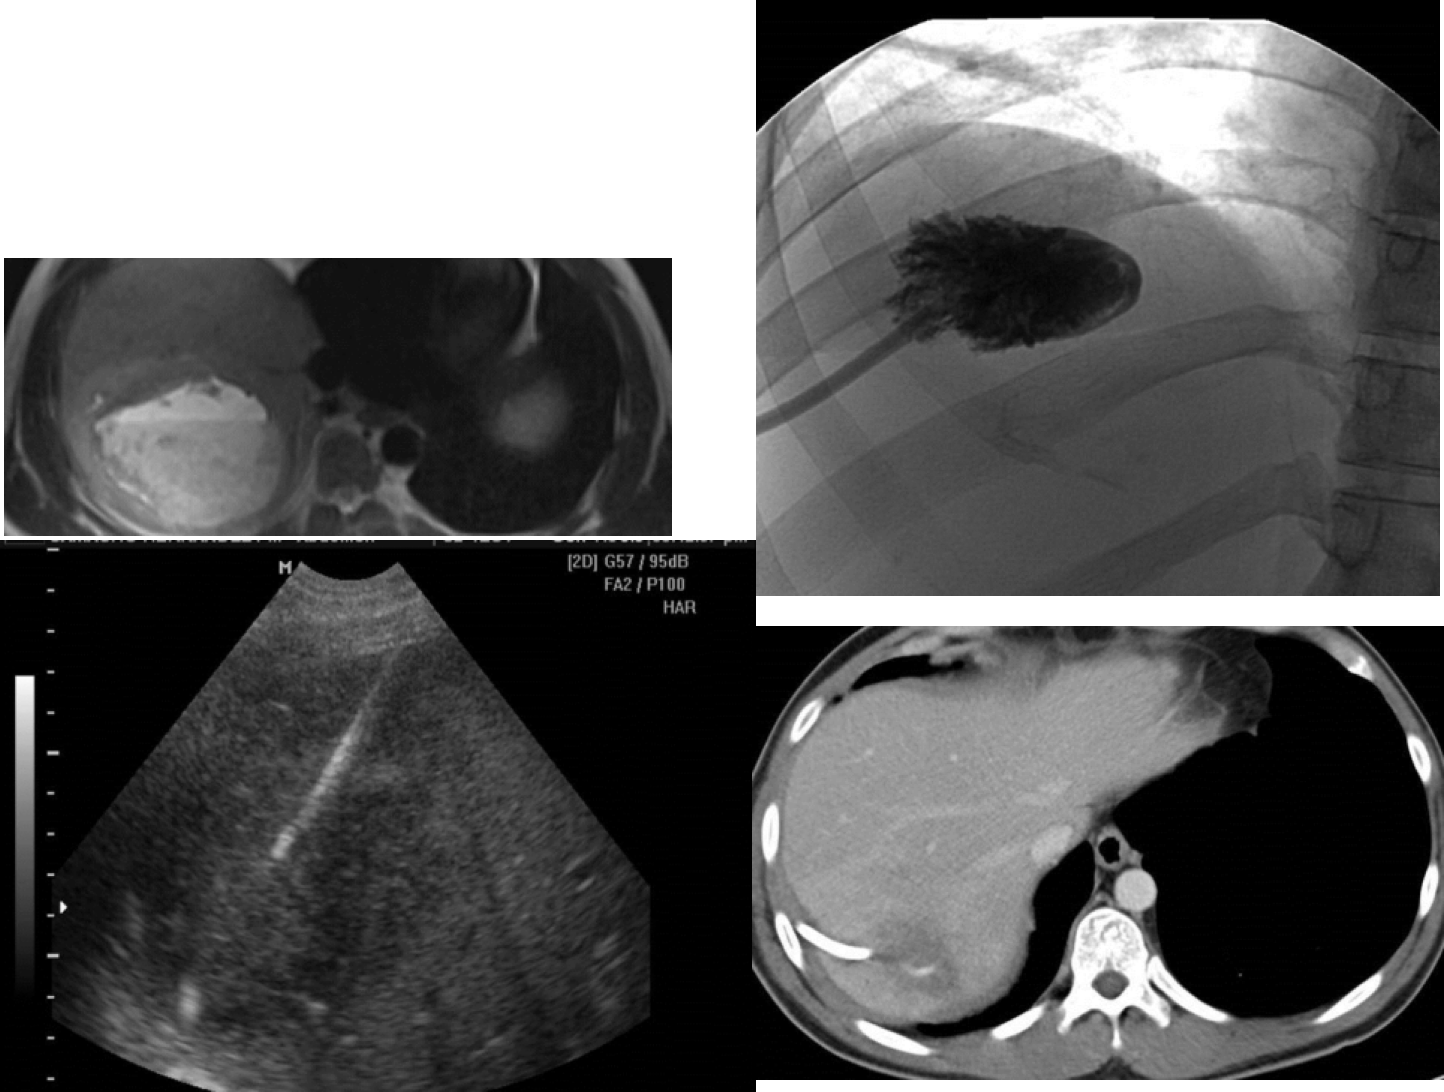

RUQ pain in a middle age patient.

Identify these four imaging modalities used in this patient?